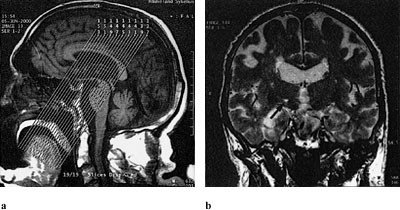

Røntgenologisk bildedanalyse viste høysignalgivende iskemiske lesjoner i kontralaterale hemisfære hos alle pasienter (tab 1). Lesjoner ble funnet i nucleus subthalamicus hos to pasienter. Hos pasient 1, hvor man fant tegn til iskemi i kontralaterale nucleus subthalamicus, så man også lette tegn til iskemi i ipsilaterale nucleus subthalamicus. Pasient 2 hadde i tillegg til høysignal i kontralateral nucleus subthalamicus også lesjoner i nucleus ventralis lateralis og nucleus ventralis posterolateralis av thalamus (fig 1). Pasient 3 hadde iskemi i globus pallidus bilateralt, men mest uttalt på kontralateral side. De øvrige tre pasienter hadde lesjoner bilateralt i forskjellige thalamuskjerner (pasient 4 i kontralaterale nucleus ventralis lateralis, pasient 5 i kontralaterale nucleus ventralis lateralis i kombinasjon med nucleus ventralis posterolateralis, pasient 6 hadde i kontralaterale nucleus ventralis posterior).

Høysignallesjon i laterale del av nucleus subthalamicus og i laterale posteriore og eventuelt ventrale posterolaterale kjerne i thalamus |

Vival symptomlindrende effekt, etter 11 måneder kun hemiballisme i overekstremitet (samt redusert kraft i arm) |